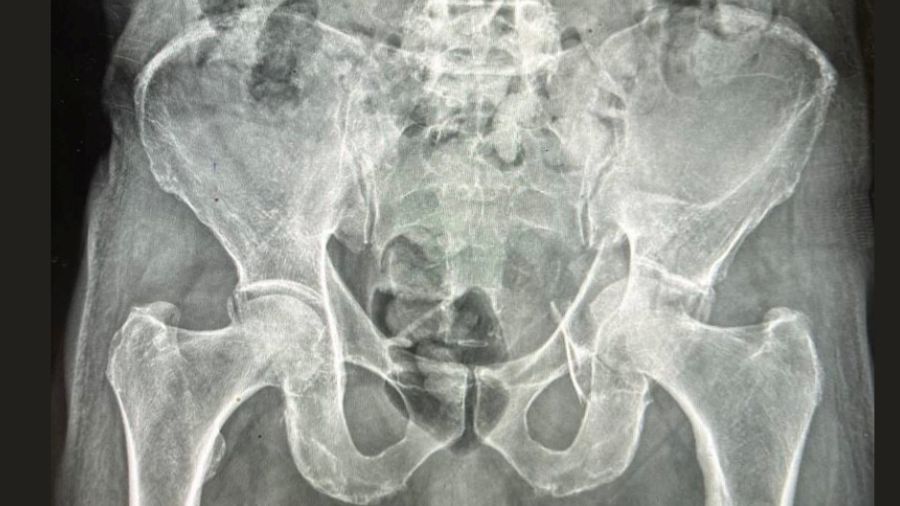

In real-world practice, treatment selection for GAFs is rarely dictated by the fracture pattern alone. Instead, surgeons must integrate multiple layers of information before committing to a course of action. Patient-related variables such as age, baseline mobility, cardiopulmonary reserve, frailty burden, and cognitive status weigh heavily in the decision process. At the same time, fracture-specific considerations—including displacement, comminution, dome impaction, posterior wall involvement, and the presence of associated pelvic injuries—directly influence both the technical feasibility of fixation and the likelihood of durable joint preservation.

Non-operative management (NOM) has traditionally been reserved for patients with minimally displaced fractures, substantial medical comorbidity, or limited functional demand. For some frail and non-ambulatory patients, this approach remains appropriate. Avoidance of anesthesia-related risks, surgical wounds, infection, and implant-related complications can be decisive advantages in carefully selected cases.

Operative management: promise, complexity, and surgeon-dependent outcomes